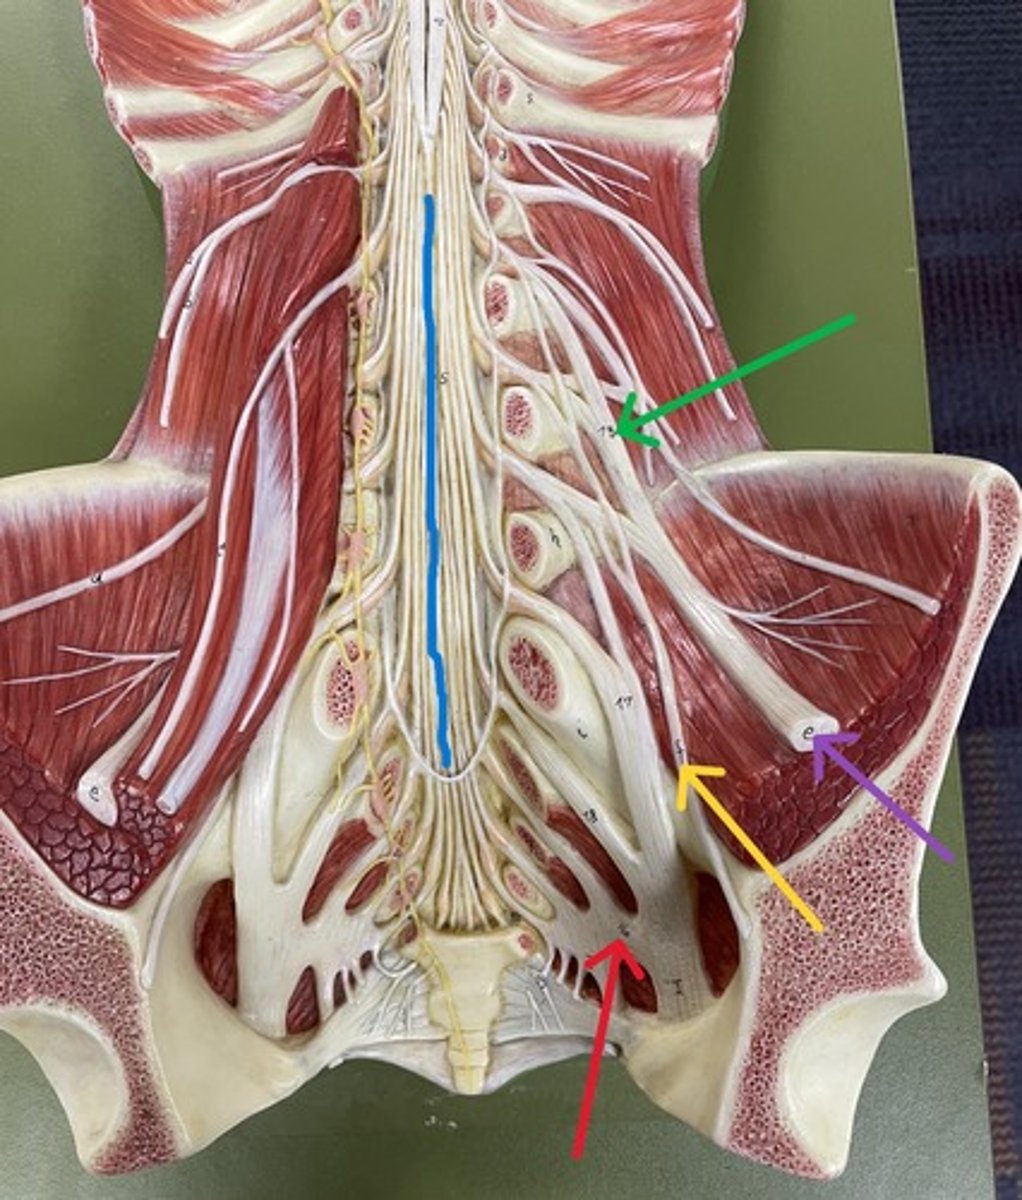

Cervical enlargement

Blue

Lumbar enlargement

Purple

Conus medullaris

Green

Cauda equina

Red

Filum terminale

blue